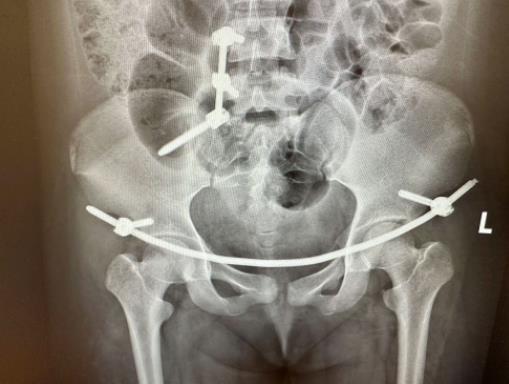

▲术后复查X线

术中,医生采用前后联合入路共切开了3个微小切口,在C形臂X光机透视定位下复位、植入腰髂钉棒+前环钉棒系统,完成了对骨盆骨折的治疗,手术过程顺利。手术对患者的损伤小,组织剥离少,未伤到重要神经、血管,且出血少,术后患者双下肢活动良好,经过一系列的术后护理及康复锻炼,目前已康复出院。

结合患者的情况,骨科团队经过讨论,决定先为患者进行右侧股骨髁上牵引复位,再实施微创经皮腰髂钉棒系统+前环钉棒系统内固定术为患者进行治疗。